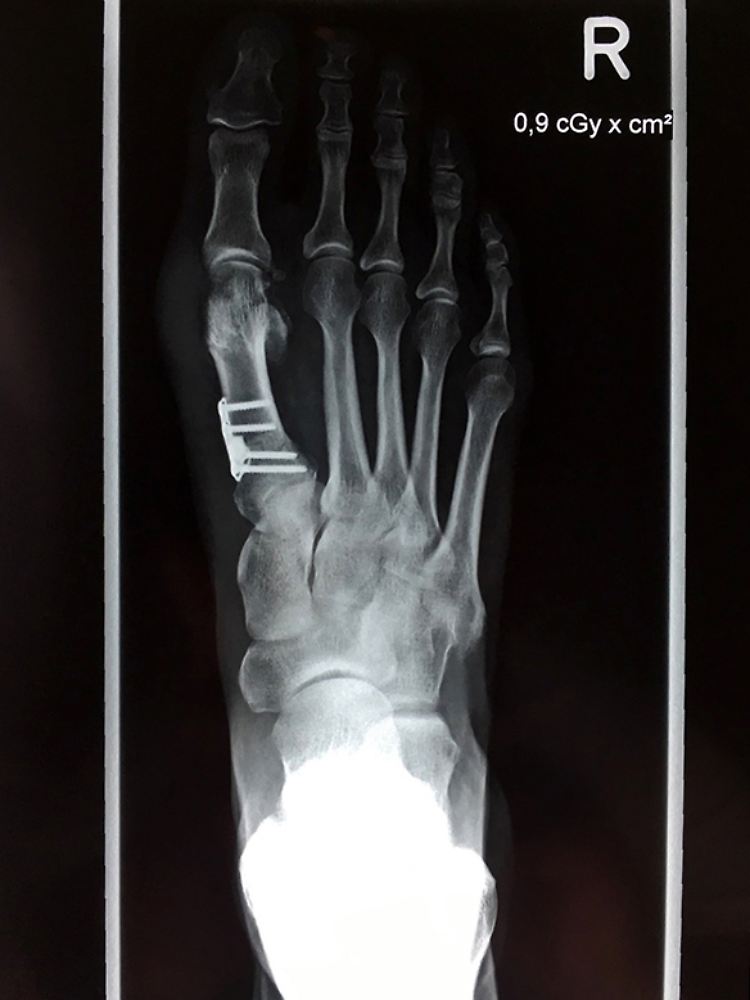

Bei diesem Fuß wurde die schiefstehende Großzehe mittels einer "Open Wedge Osteotomie" korrigiert. Dabei wird der Fuß verschmälert und unter anderem eine Titanplatte mit Abstandhalter verschraubt, die später wieder entfernt wird. Ziel ist, dass die große Zehe am Ende von allein gerade steht.

(Foto: dpa)